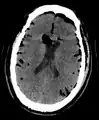

Pneumocephalus

Pneumocephalus and comminuted fracture of the frontal sinus

Pneumocephalus is the presence of air or gas within the cranial cavity. It is usually associated with disruption of the skull: after head and facial trauma, tumors of the skull base, after neurosurgery or otorhinolaryngology, and rarely, spontaneously. Pneumocephalus can occur in scuba diving, but is very rare in this context.

CT scans of patients with a tension pneumocephalus typically show air that compresses the frontal lobes of the brain, which results in a tented appearance of the brain in the skull known as the Mount Fuji sign.[1][2][3] The name is derived from the resemblance of the brain to Mount Fuji in Japan, a volcano known for its symmetrical cone. In typical cases, there is a symmetrical depression near the midline (such as the crater of a volcano), due to intact bridging veins.[3] Its occurrence seems to be limited to tension pneumocephalus (not occurring in pneumocephalus without tension).[4] The sign was first described by a team of Japanese neurosurgeons.[5]